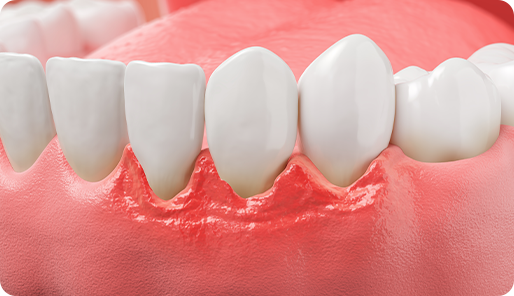

붓고 피나는 잇몸병의 주된 원인은,

바로 치태와 치석입니다.

치태

치석의 전 단계로, 치아 표면에 세균이 특정한 타액과

만나서 생긴 끈끈하고 투명한 세균막입니다.

치석

치아 표면에 있는 세균막이 각종 타액과 함께 침착되어

만들어진 것으로 세균과 무기질로 이루어진 딱딱한

세균 덩어리이며, 치주 질병의 주요 원인입니다.

소리 없이 진행되는 풍치는 치아를 상실하는

가장 큰 원인이므로

조기 발견, 치료가 중요합니다!

1단계 I 건강한 잇몸

(치주낭 3mm 이하)

연 1회 스케일링으로 플라그와 치석을 제거,

올바른 칫솔질과 치실 및 치간칫솔을 사용하여 청결한

구강상태를 유지

2단계 I 치은염

(치주낭 3~5mm 이하)

잇몸 하방에 부착된 치석과 플라그를 스케일링 및 치근활택술로 깨끗하게 제거, 일시적으로 시린 증상 발생

3단계 I 초기 치주염

(치주낭 5~7mm 이하)

잇몸 하방에 다량의 치석 및 염증을 치주소파술로 깨끗하게 제거, 잇몸뼈 손실을 방지, 일시적으로 시린 증상 발생

4단계 I 중기 치주염

(치주낭 7mm 이상)

잇몸뼈 손실이 뿌리 부분 1/2 이상이 녹은 상태로 치아가

많이 흔들림. 판막술로 잇몸 절개 후

염증 및 치석을 제거